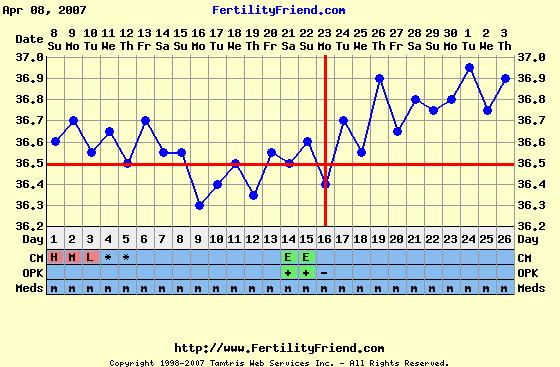

A peteérés megfigyelésére a hőmérőzés jó megoldás, illetve a hüvelyi nyák figyelése, ami félidő táján - tehát peteéréskor - tojásfehérje-szerüvé válik, ez jelzi a közelgő peteérést. A módszert Billings-módszernek hívják, utána tudsz nézni a neten.

Van még olyan hogy LH teszt, ami szintén a peteérést hivatott jelezni, de van már rá több példa is - igaz Lafika ?